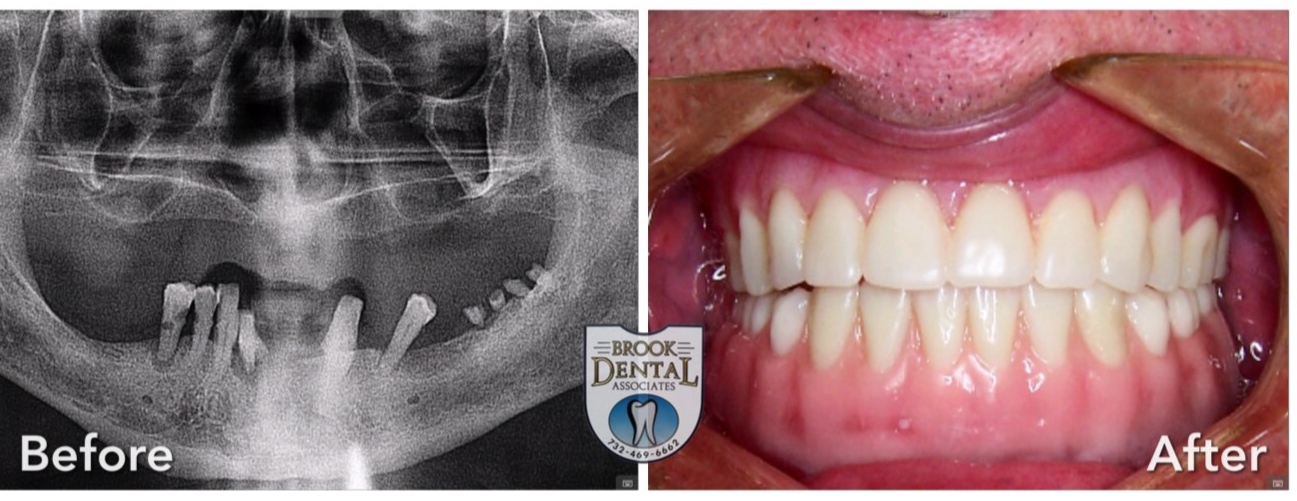

ALL ON FOUR (IMPLANT SUPPORT RESTORATION)

Here are some photos of our actual patient's results! Looking for your smile transformation? Don't wait! Call Brook Dental Associates today at (732) 469-6662.